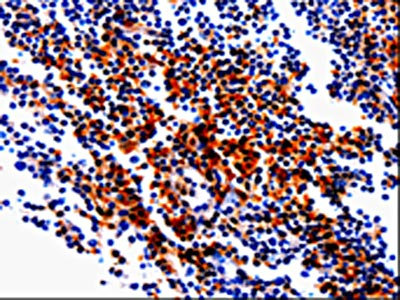

The image on the left is immunohistochemistry of paraffin-embedded Human tonsil tissue using CSB-PA838764(GDI1 Antibody) at dilution 1/20, on the right is treated with fusion protein. (Original magnification: ×200)